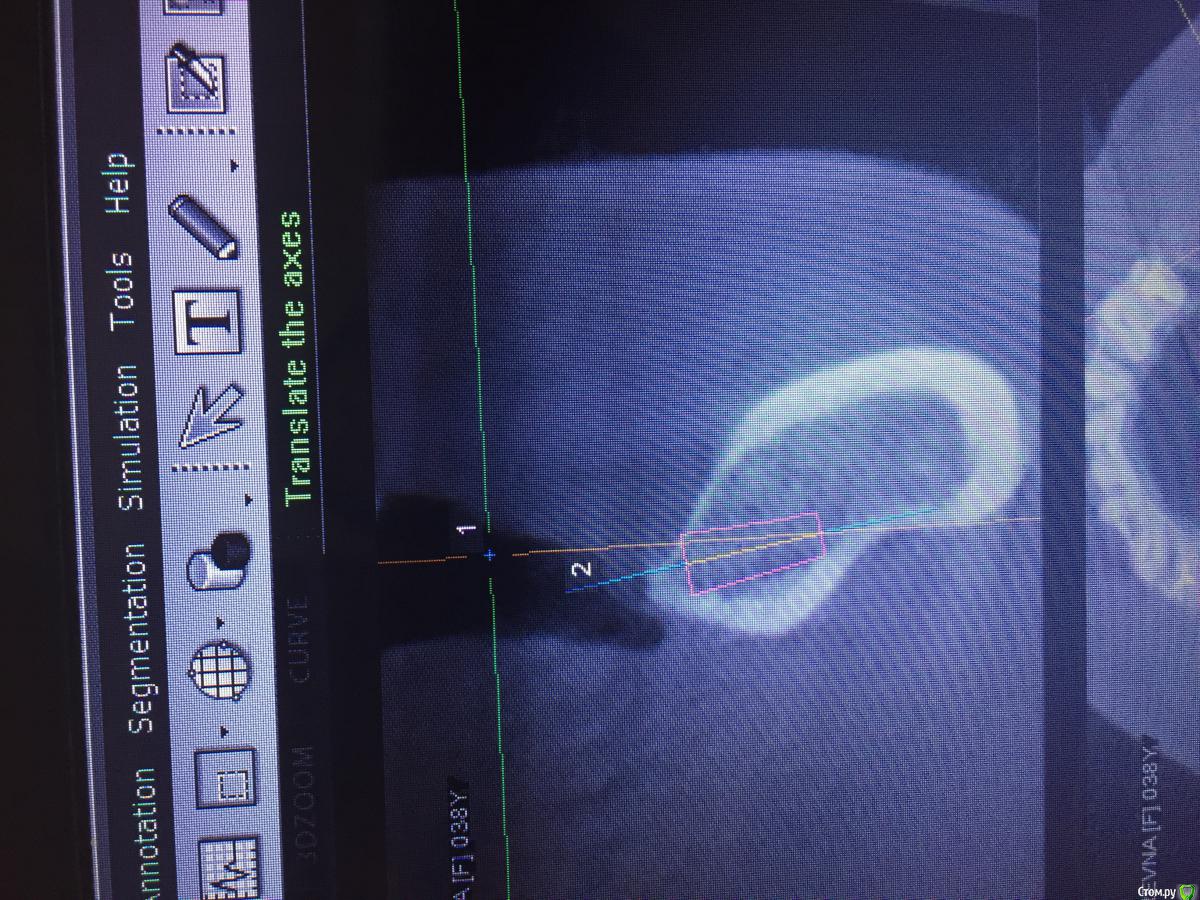

Evikrol Опубликовано 1 мая, 2015 Автор Поделиться Опубликовано 1 мая, 2015 (изменено) Как правильно спозиционировать имплантат? Если есть язычное поднутрение? Это 10, может 8мм? Почему изображение свалилось:-)? Как тут перевернуть:-)) Изменено 1 мая, 2015 пользователем Evikrol Ссылка на комментарий

Evikrol Опубликовано 1 мая, 2015 Автор Поделиться Опубликовано 1 мая, 2015 (изменено) может 8 и не боятся ничего. Да чтож они переворачиваются! Или ауто под надкостницу положить? Изменено 1 мая, 2015 пользователем Evikrol Ссылка на комментарий

faity Опубликовано 1 мая, 2015 Поделиться Опубликовано 1 мая, 2015 область нижней шестерки? по идее 4,5/8 должно хватить, но зачем? ставьте вестибулярнее и 11 войдет на ура до 4,0. Ссылка на комментарий